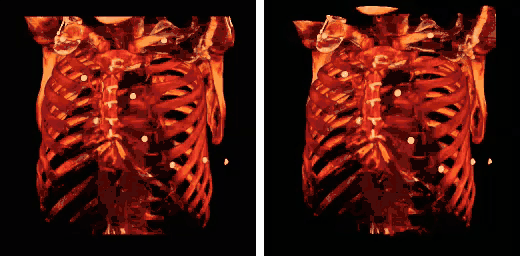

Note also that the colour look-up table (CLUT) can be varied to highlight features of particular interest, as shown in the set of images below:

The influence of the opacity table is illustrated in the following example images: